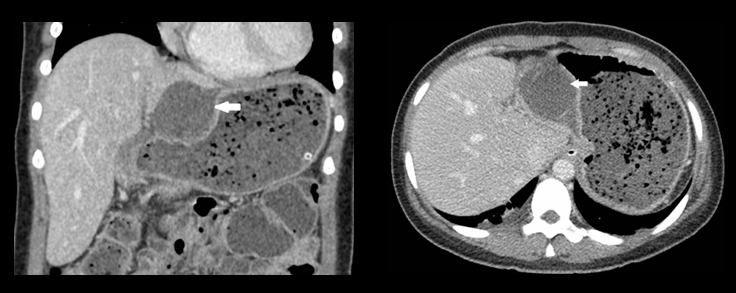

入院12h,患者自述腹痛加剧伴发热,腹部检查示右上腹压痛和肌卫,墨菲氏征阴性。实验室检查显示白细胞计数升高(13,300 /μL),中性粒细胞占比86%。腹部CT 检查显示胆囊体和底部从胆囊窝移位至肝胃隐窝,胆囊明显肿胀伴胆囊壁弥漫性增厚,无不透光结石,胆囊壁增强减弱(图1)。基于上述发现,诊断为胆囊扭转伴急性非结石性胆囊炎。

检查显示胆囊体和底部从胆囊窝移位至肝胃隐窝,胆囊明显肿胀伴胆囊壁弥漫性增厚,无不透光结石,胆囊壁增强减弱(图1)。基于上述发现,诊断为胆囊扭转伴急性非结石性胆囊炎。

(图1 CT检查 )